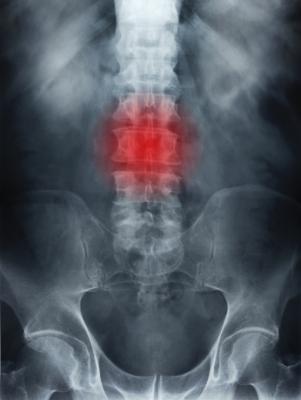

Sciatica is pain that originates along the sciatic nerve, which extends from the back of the pelvis down the back of the thigh. The sciatic nerve is the largest nerve in the body. Treatments to relieve pain include nonsteroidal anti-inflammatory medications, applying heat or cold, and exercising to help minimize inflammation. When the pain is caused by a lumbar disc herniation, surgery is often the treatment option for pain relief.

Another treatment that researchers have studied for sciatica pain relief is pulsed radiofrequency—a minimally invasive procedure in which pulses of energy from a probe are applied directly to nerve roots near the spine.

A total of 351 participants (223 men) with sciatica were randomly assigned to receive a single CT-guided pulsed radiofrequency treatment combined with TFESI (174 patients) or TFESI alone (177 patients). Participants were recruited at two tertiary university hospitals and one spine clinic. All procedures were carried out in an outpatient clinic, took only 10 minutes and were performed without general anesthesia.